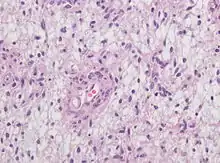

Histopathology specimen of Angiocentric glioma, higher magnification, HE stain

Neuropathology is a specialty within the study of pathology focused on the disease of the brain, spinal cord, and neural tissue.[33] This includes the central nervous system and the peripheral nervous system. Tissue analysis comes from either surgical biopsies or post mortem autopsies. Common tissue samples include muscle fibers and nervous tissue.[34] Common applications of neuropathology include studying samples of tissue in patients who have Parkinson's disease, Alzheimer's disease, dementia, Huntington's disease, amyotrophic lateral sclerosis, mitochondria disease, and any disorder that has neural deterioration in the brain or spinal cord.[35][36]